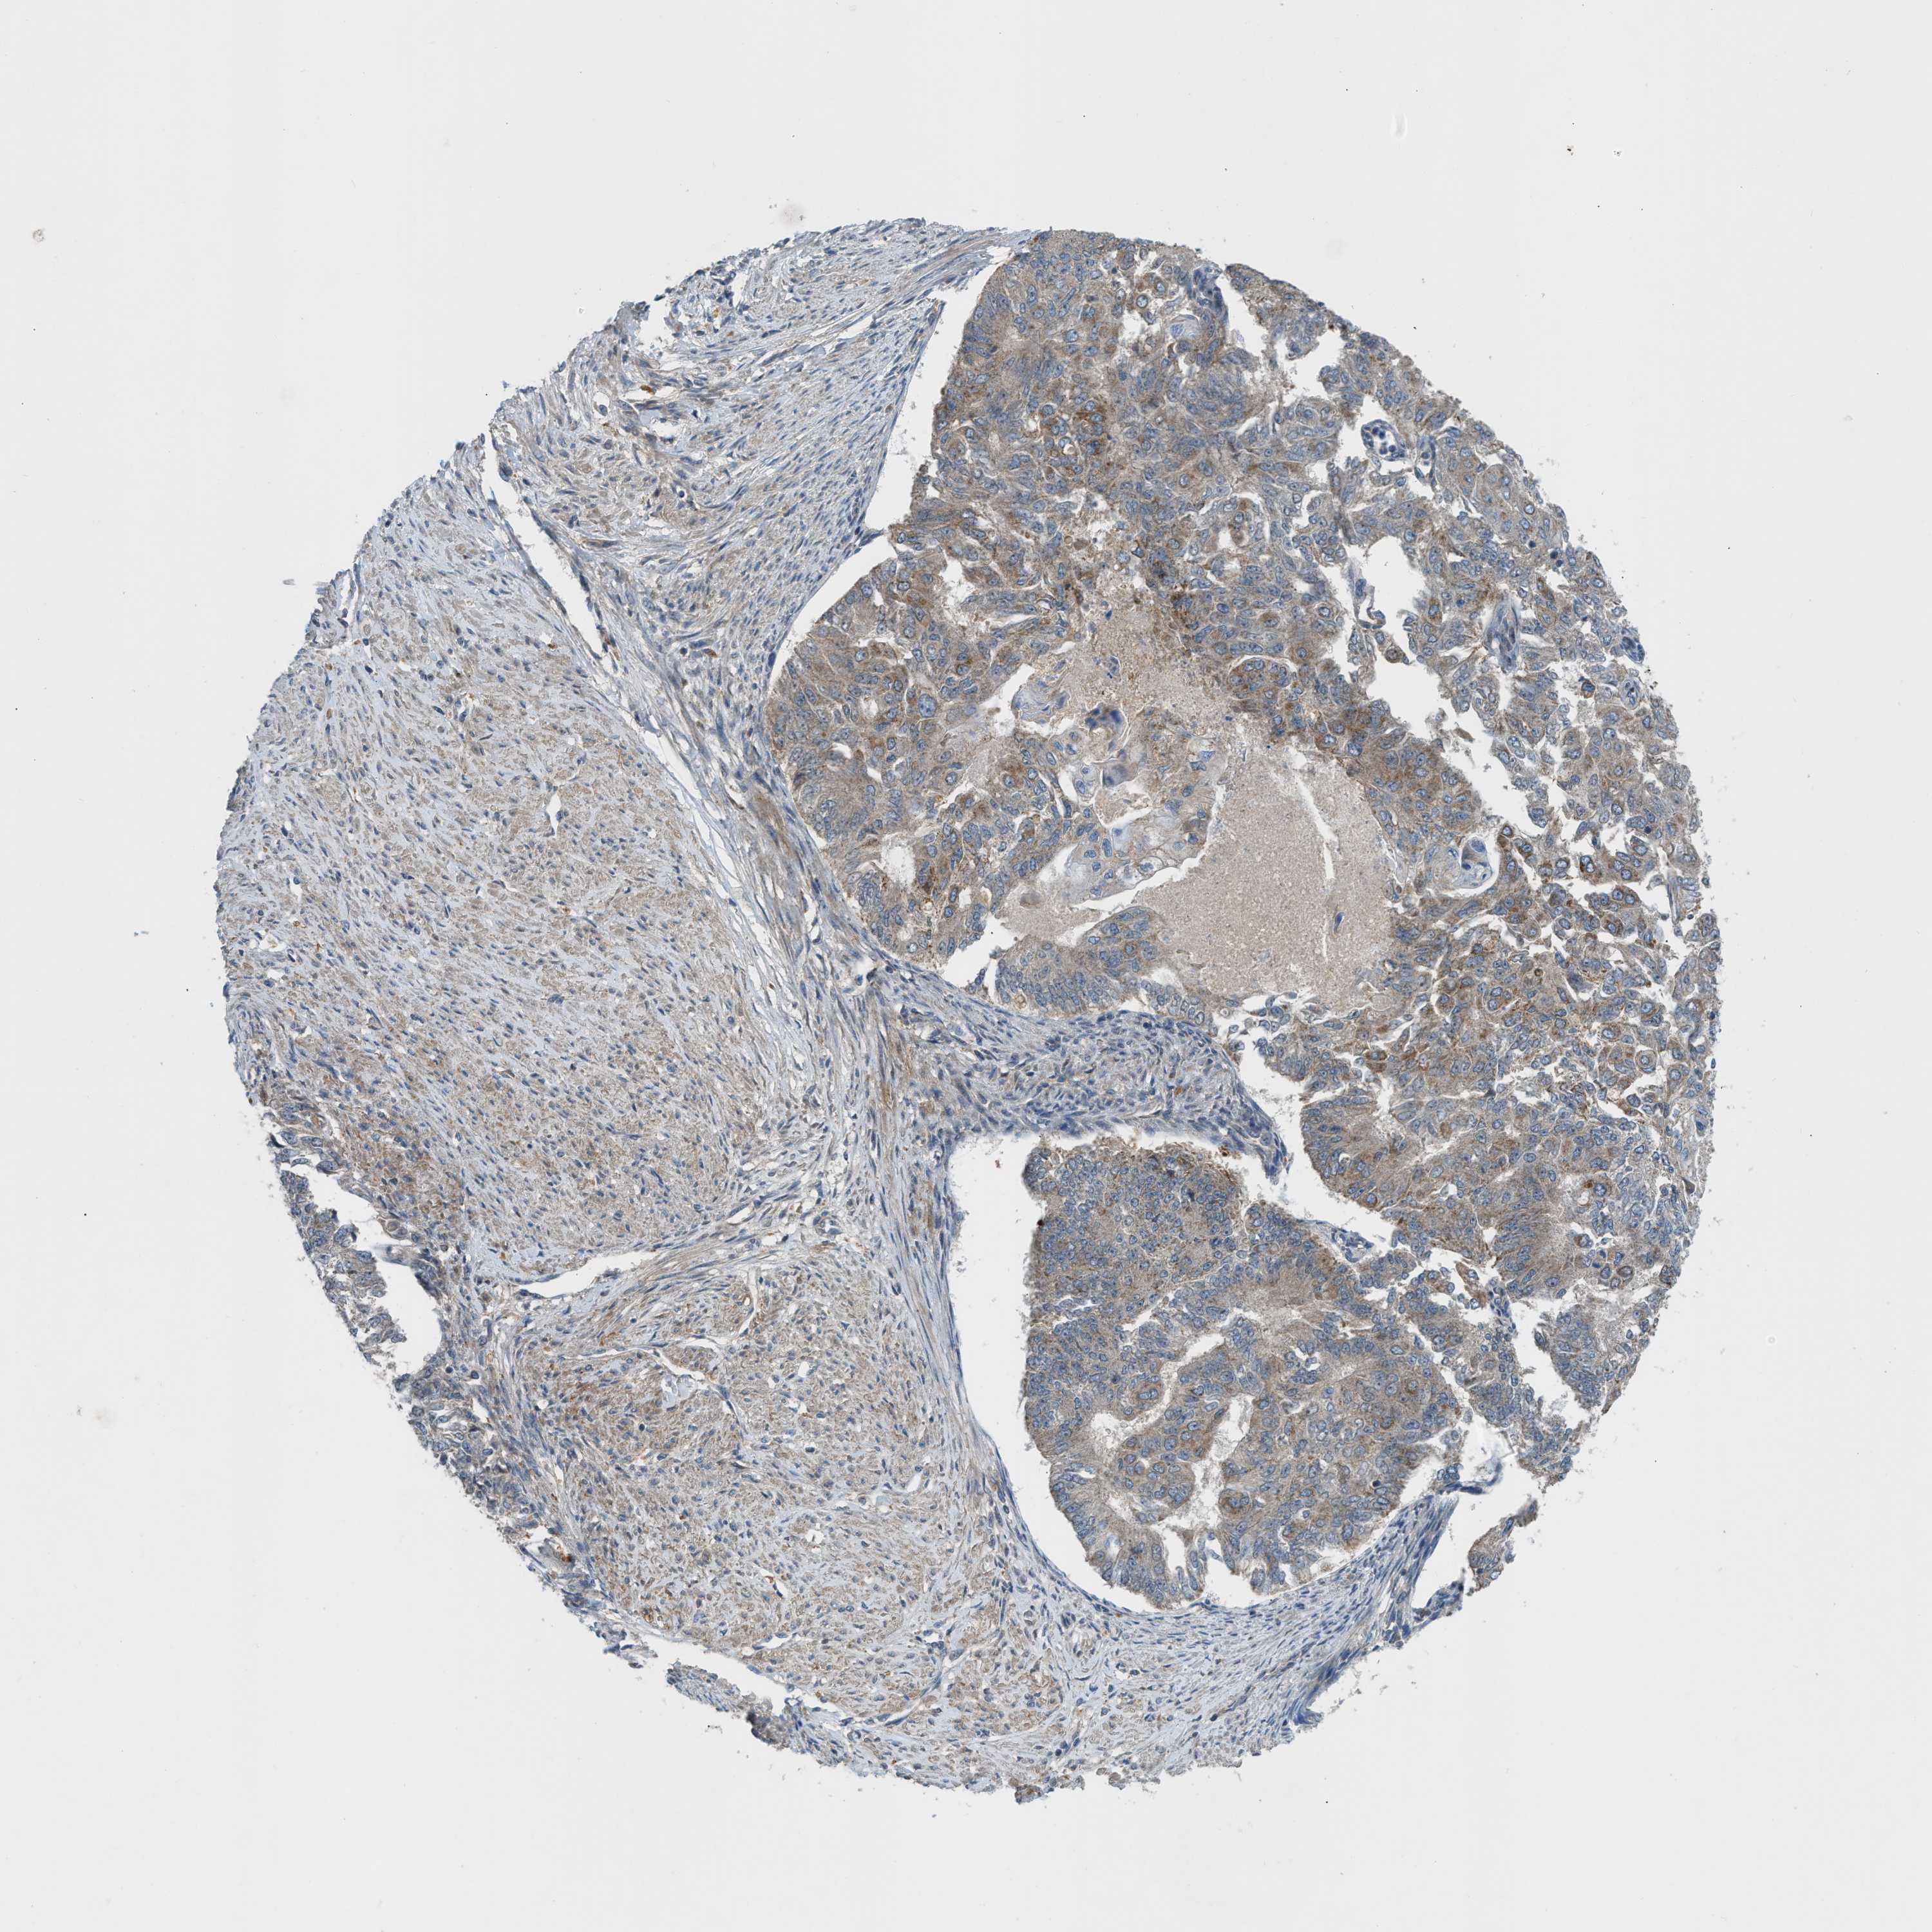

ENDOMETRIAL CANCER - Protein expressioni

A mouse-over function shows sample information and annotation data. Click on an image to view it in a full screen mode. Samples can be filtered based on level of antibody staining by selecting one or several of the following categories: high, medium, low and not detected. The assay and annotation is described here.

Note that samples used for immunohistochemistry by the Human Protein Atlas do not correspond to samples in the TCGA dataset.

Antibody stainingi

Antibody staining in the annotated cell types in the current human tissue is reported as not detected, low, medium, or high, based on conventional immunohistochemistry profiling in selected tissues. This score is based on the combination of the staining intensity and fraction of stained cells.

Each image is clickable and will lead to virtual microscopy that enables deeper exploration of all samples and also displays staining intensity scores, fraction scores and subcellular localization as well as patient and tissue information for each sample.

Antibody HPA018124

Staining

High

Medium

Low

Not detected

Intensity

Strong

Moderate

Weak

Negative

Quantity

>75%

75%-25%

<25%

None

Location

Nuclear

Cytoplasmic/membranous

Cytoplasmic/membranous,nuclear

Adenocarcinoma, NOS

Adenoma, NOS